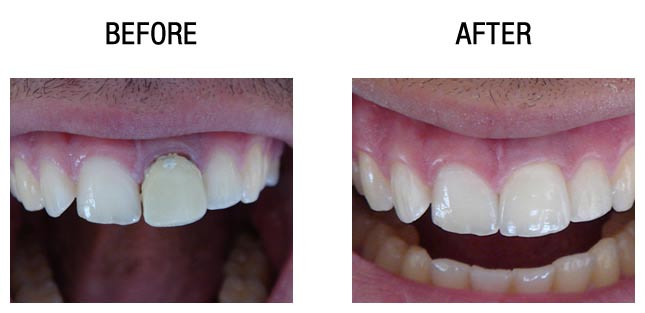

种植牙前后对比

种植牙前后对比